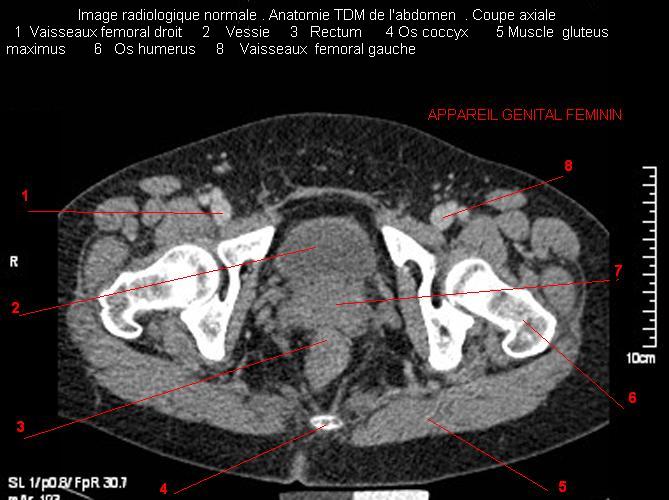

Images radiologique TDM normale de l'abdomen et tube digestif  en coupe axiale ( CT scanner )  :

Coupe axiale     Coupe frontale      Coupe  sagitale